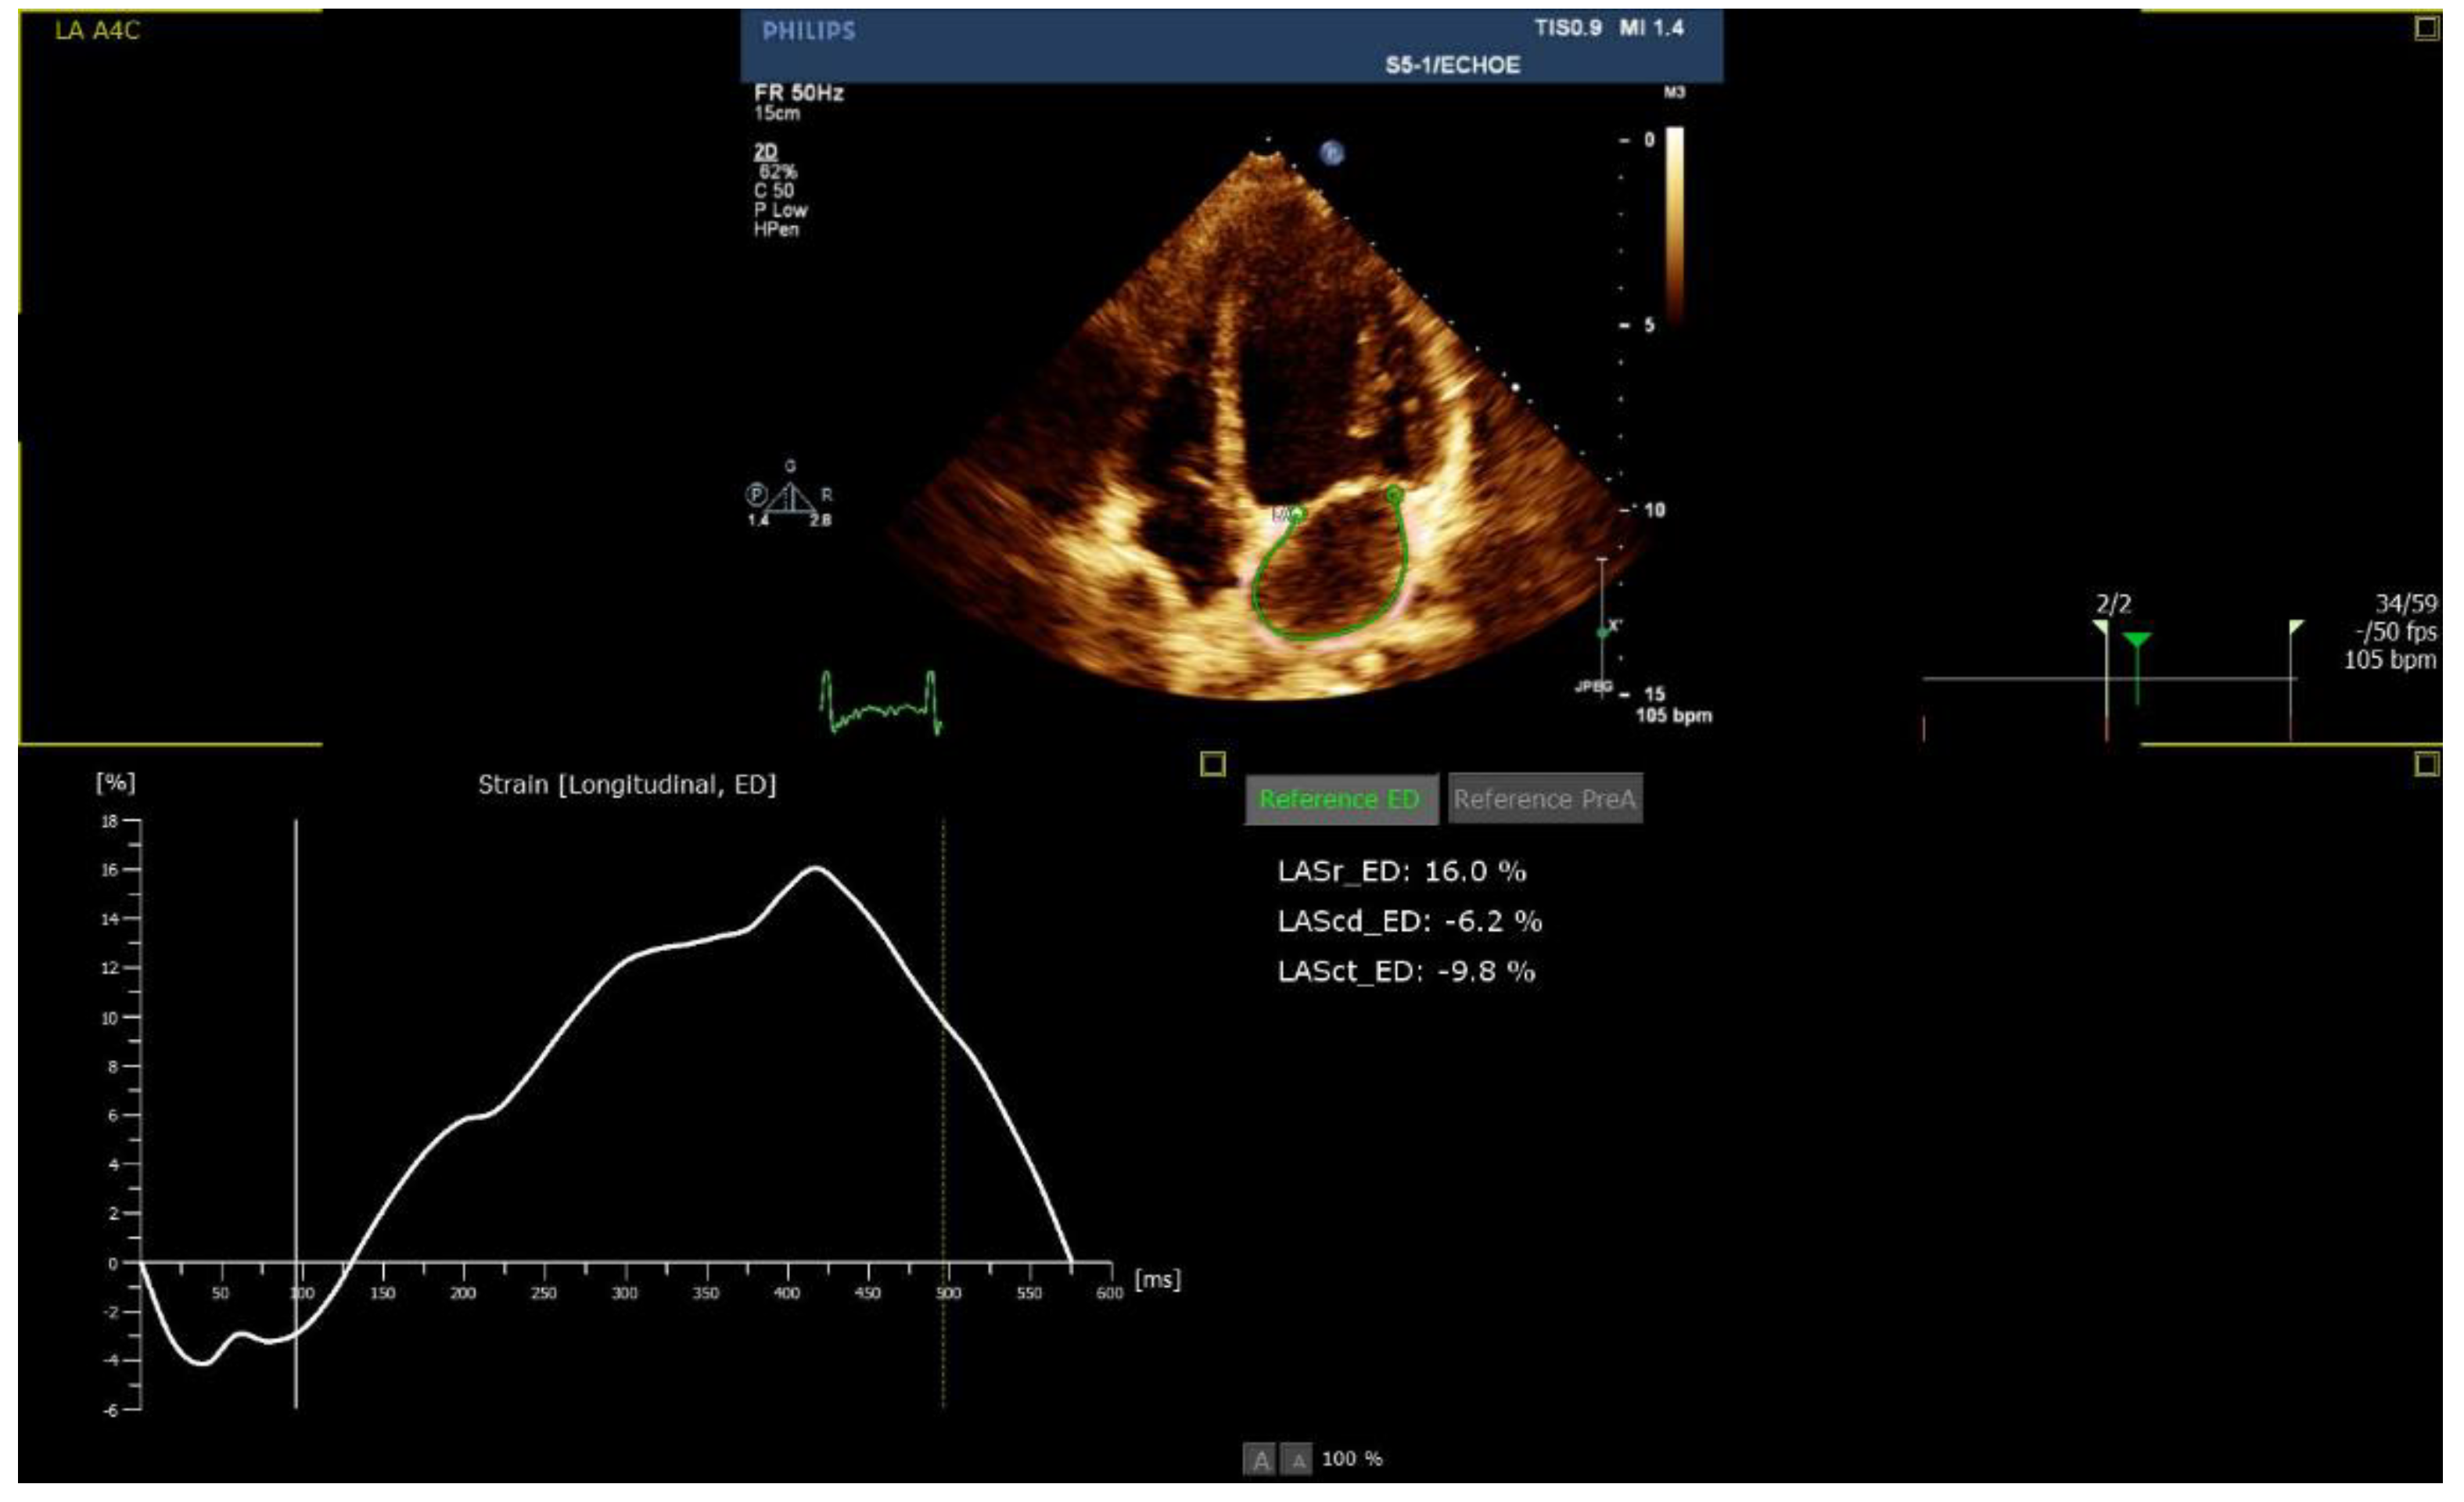

| LA reservoir (%), mean (SD) | 32 (±12) | 33 (±12) | 44 (±14) | 0.066 |

| LA conduit (%), mean (SD) | 17 (±11) | 30 (±7) | 37 (±11) | 0.001 |

| LA pump (%), mean (SD) | 19 (±8) | 7 (±3) | 10 (±4) | 0.001 |